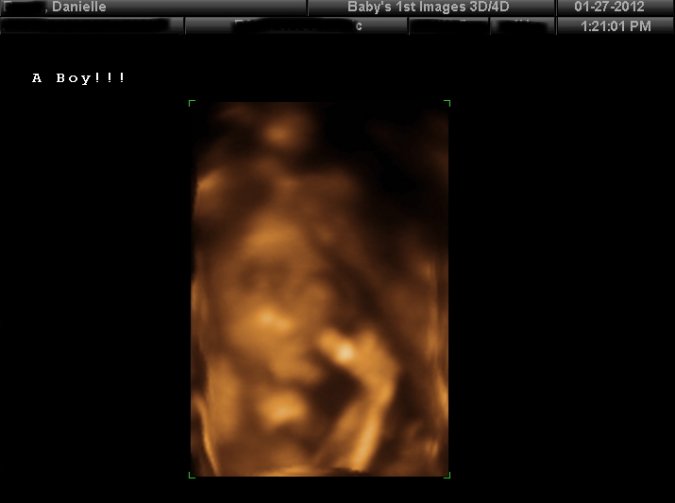

Danielle's grandmother give her a 3D ultrasound as a gift.

Here is the face of the little boy to be born.  Cute!